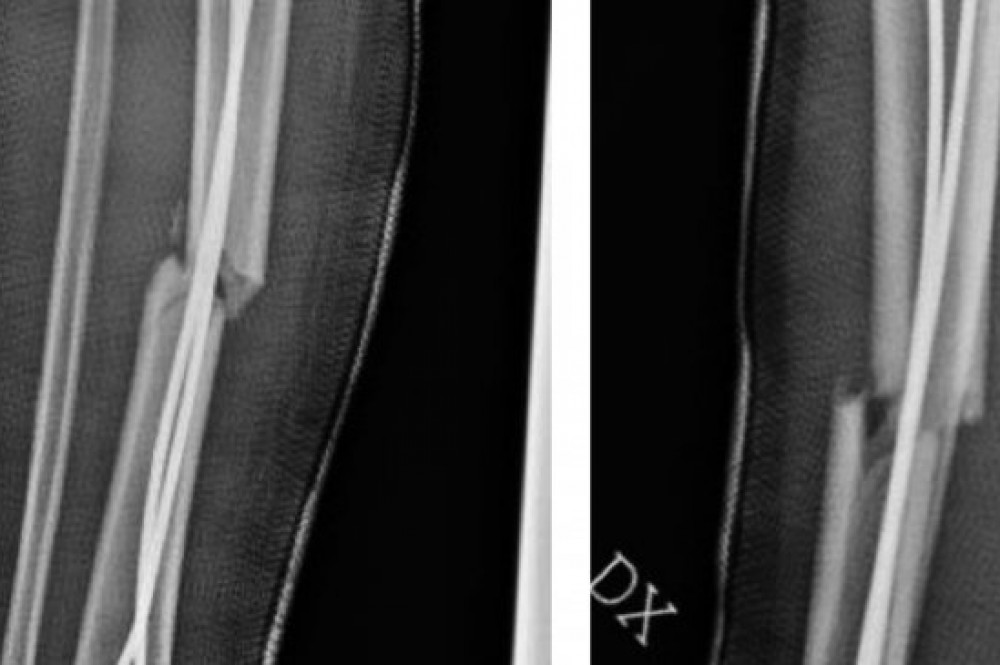

La tibia o shinbone è l'osso più grande che si trova nella parte inferiore della gamba rispetto al perone e insieme a quest'ultimo è una delle ossa più comunemente fratturate nel corpo. È utile specificare che nei bambini, è possibile che la frattura non sia immediatamente visibile nelle radiografie iniziali ed è. La causa principale di questo tipo di frattura sono. È una delle ossa più comunemente fratturate e questo può accadere in seguito ad una. Le fratture nei bambini hanno caratteristiche particolari. Cos'è la frattura della tibia? Cara maria, fino a poco tempo addietro per guarire da una frattura composta di tibia e perone ci volevano da 5 a 7 mesi di tempo. La gamba è composta da 2 ossa lunghe: Riabilitazione da frattura tibia e perone. Esempio di asimmetria tra la crescita della tibia e del perone. Buonasera probabilmente la lesione della tibia è una frattura composta. La tibia è un osso che può andare incontro a fratture ad alto impatto. Fratture di femore e tibia. La tibia è la più grande delle due ossa nella parte inferiore della gamba. Trauma a bassa energia come cadute al suolo o traumi sportivi. Fra ttura osso zigomatico o il bambino ha riportato fratture a tibia , femore e perone scomposte e trauma cranico. Cosa distingue le fratture dei bambini da quelle degli adulti.